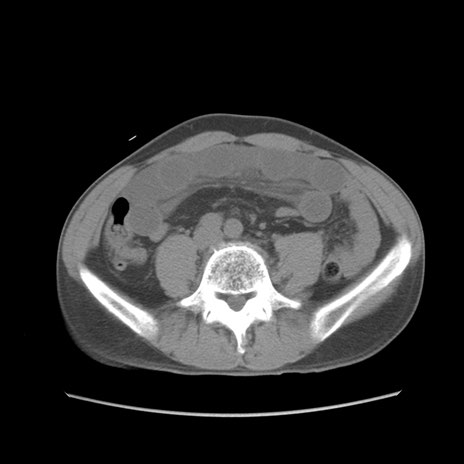

症例56 CT(横断像)

脂肪ウインドウ